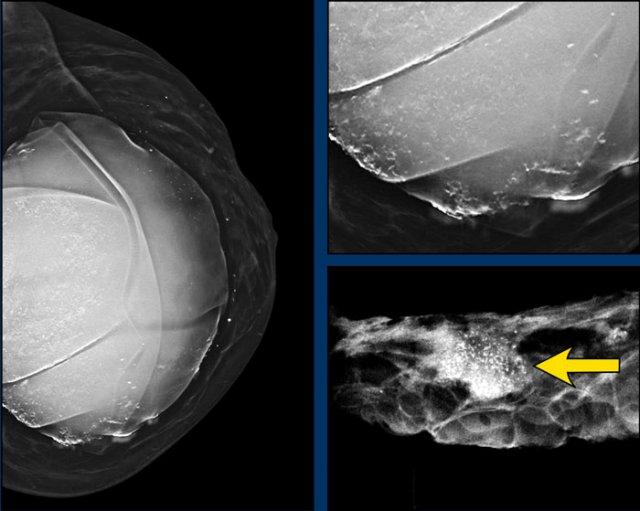

Trên nhũ ảnh này, có cả vôi hóa trong bao xơ lẫn vôi hóa ngoài bao xơ không điển hình.

Hình ảnh chi tiết của bệnh phẩm cho thấy khối và các vôi hóa tập trung thành nhóm.

Giải phẫu bệnh: ung thư vú độ 2, không có loại đặc biệt (NST – No Special Type).